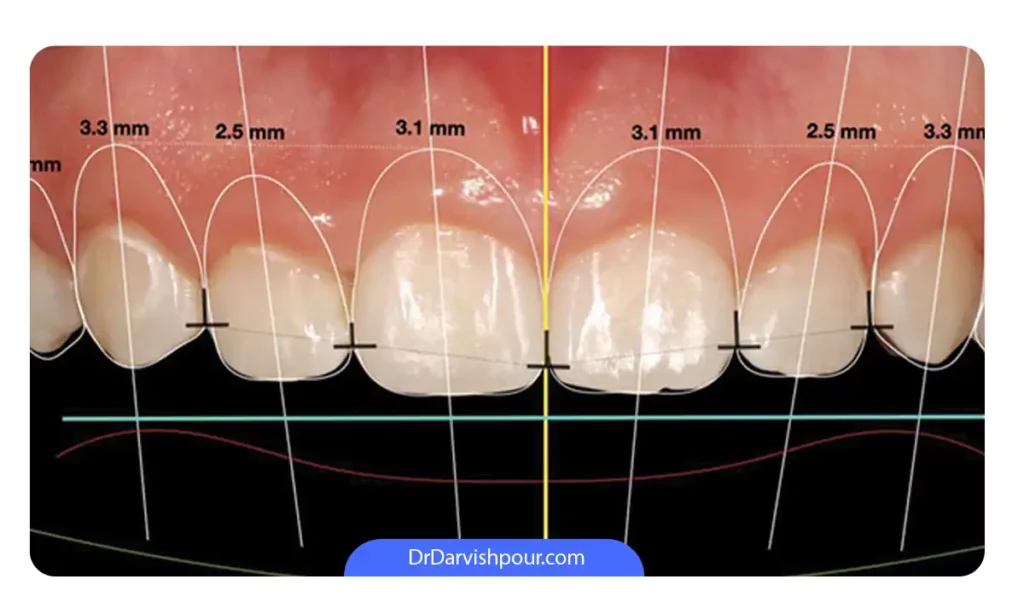

7. عمل جراحی زیبایی لثه یا کانتورینگ لثه (Gum contouring surgery)

کانتورینگ لثه یک روش کم تهاجم است که شامل تغییر شکل جزئی، ایمن و دقیق خط لثه می شود. با برداشتن بافت اضافی لثه که روی دندان ها را گرفته، خط لثه عقب تر می رود و طول تاج دندان نیز افزایش می یابد. این روش به بهبود زیبایی و هماهنگی لبخند کمک می کند.